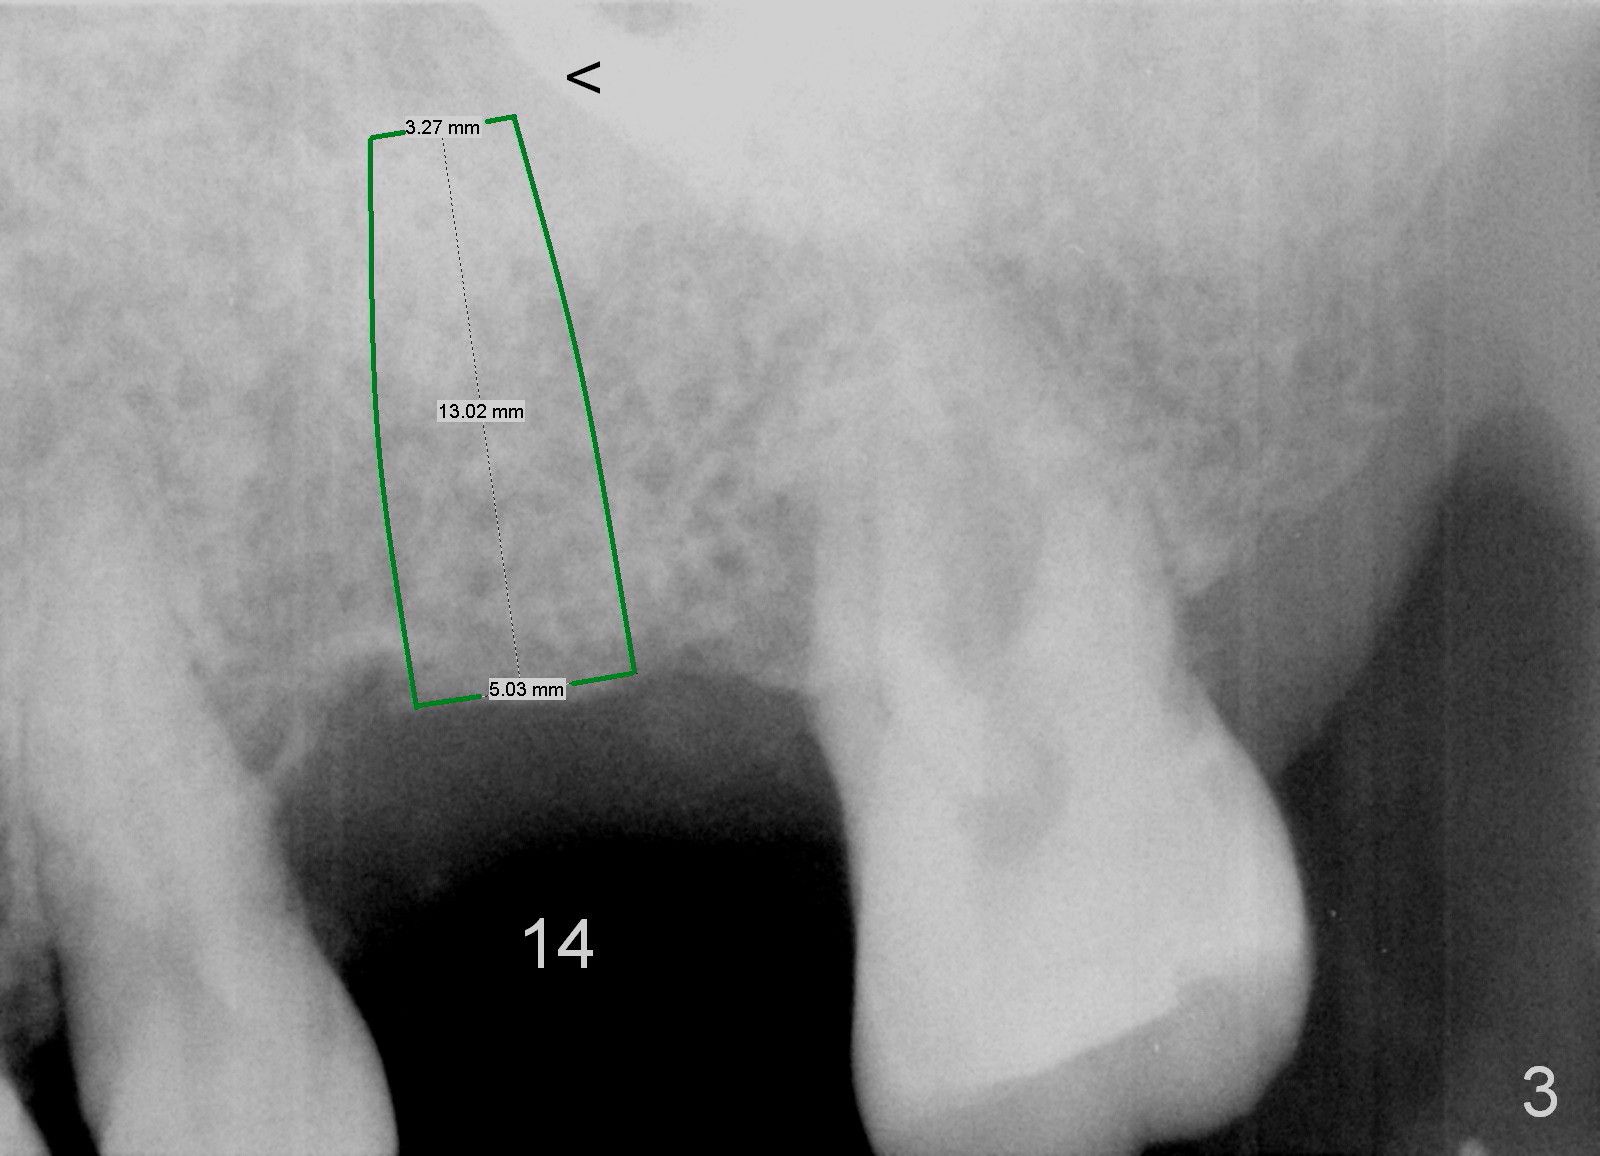

Implant placement at #31 reveals that bone width (bucco-lingual) is not a problem for a 64-year-old man. He requests implant placement at #7 and 14 (Fig.1,3), because the upper flipper has been lost. He wants to make sure that the implant at #7 does not cause the pain at #6. In fact the flipper appears to have lead to caries (Fig.2 *) and periapical radiolucency (<) at #6. RCT is rendered at #6 prior to a 1-piece implant at #7 (Fig.1). Since bone height is sufficient, the implants do not have to penetrate the nasal floor (Fig.1 v) or the sinus floor (Fig.3 <) unless the bone density is low. Prepare implant positioner of 4 mm to determine whether the ridge is wide to hold a 3.8 or 4 mm implant. Take preop photos to show the ridge width.